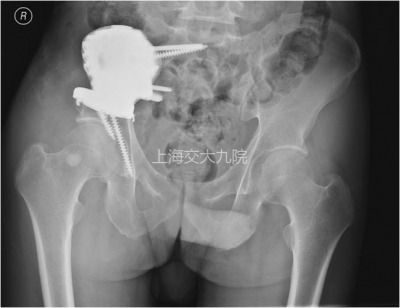

图4  术后X线片。右上图示下方两枚螺钉正好固定于髋臼前、后壁且未进入关节间隙,骶骨下方的突起与锁定螺钉有助于将剪切应力转变为压应力,骶骨上部的两枚螺钉避开了骶神经